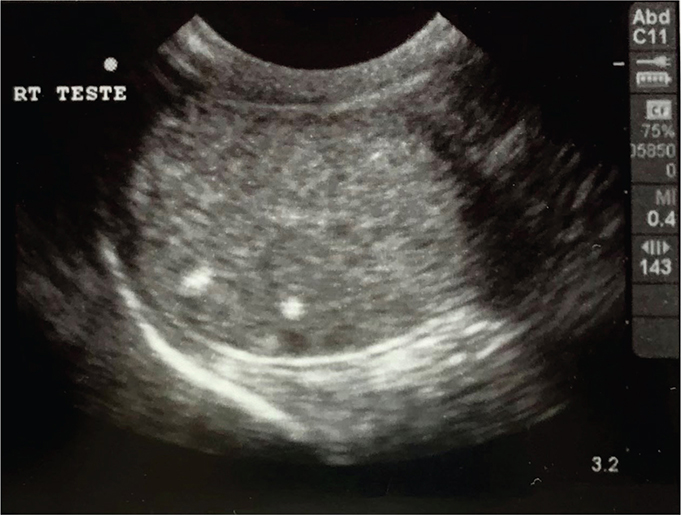

Case 1: A 3½ year, intact male Treeing Walker Coonhound, was presented for ultrasonographic evaluation of the abdomen and testes due to weight loss and polyphagia in July of 2021. Semen had not been evaluated, but the dog had sired a litter in 2020. Left testis appeared normal and had a coarse medium echogenicity throughout; right testis contained hyperechoic foci that were slightly larger than typical testicular microliths observed in human beings but were identical to TM in all other aspects (Figure 1). Other findings on abdominal ultrasonography included a complex cystic structure in the right kidney. Ultrasonography of the testes was repeated in October of 2021 and July of 2022, with no changes noted from the original ultrasonography. In October of 2022, the dog was castrated, due to concern about testicular microlithiasis, a couple of episodes of prostatitis, and retirement from breeding. Right testis was submitted for histopathology; 2 discrete and relatively small foci of intratubular mineralization accompanied by surrounding fibrosis were noted. In these foci, aggregates of fragmented basophilic material, interpreted to represent mineralization, were present within shrunken seminiferous tubules surrounded by a moderate amount of fibrosis (Figures 24) without associated inflammation.

Figure 1.

Figure 1. Testicular ultrasonographic image of Case 1